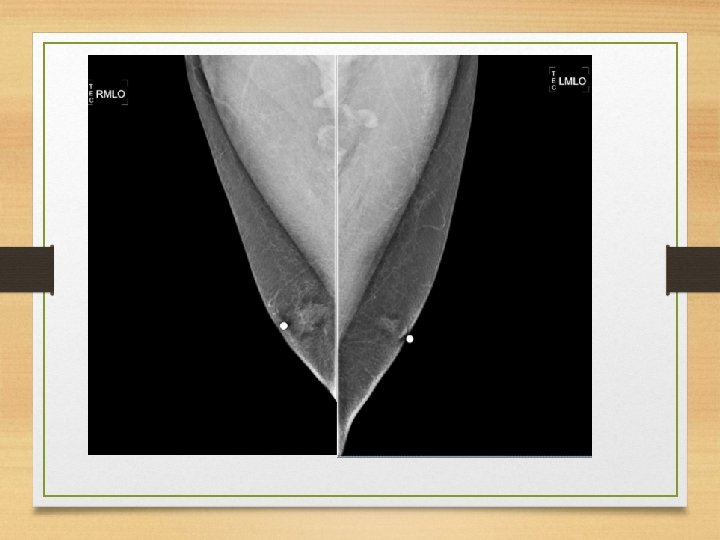

Mama masculina

Posición de la mama masculina • Se coloca similar a una mama femenina pequeña. • La OML se usa para obtener imágenes en proyección lateral. • La CC se puede hacer caudocraneal.